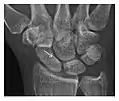

Triquetral fracture usually occurs on the dorsal aspect by impingement from the ulnar styloid or avulsion of strong ligamentous attachment. The dorsal avulsion fracture or "chip fracture" appears as a small bony fragment on the dorsal aspect of the triquetrum and is best detected on the lateral view(Figure 4). When radiography is negative in patients with high suspicion of a fracture, both MRI and MDCT will be of value. However, it has been shown that MRI is superior for detecting trabecular fractures in carpal bones.

Figure 4: Dorsal triquetral fracture of the left wrist in a 30-year-old man after a trauma. (a) Anteroposterior radiograph shows a normal appearance. (b) Lateral radiograph of the same wrist demonstrates a chip fracture off the dorsal aspect of the triquetrum (arrow).[1]